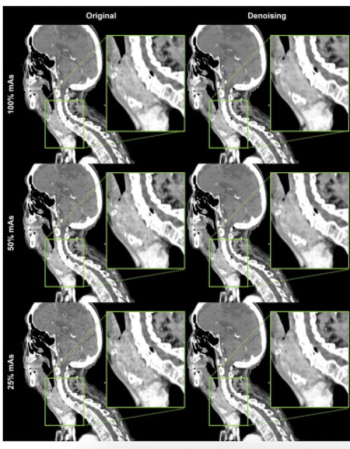

Offering comparable sensitivity to radiologists for detecting contralateral breast cancer on mammography images, an emerging adjunctive AI software may also facilitate earlier diagnosis, according to study findings presented at the at the 2024 American Society of Clinical Oncology (ASCO) Annual Meeting.